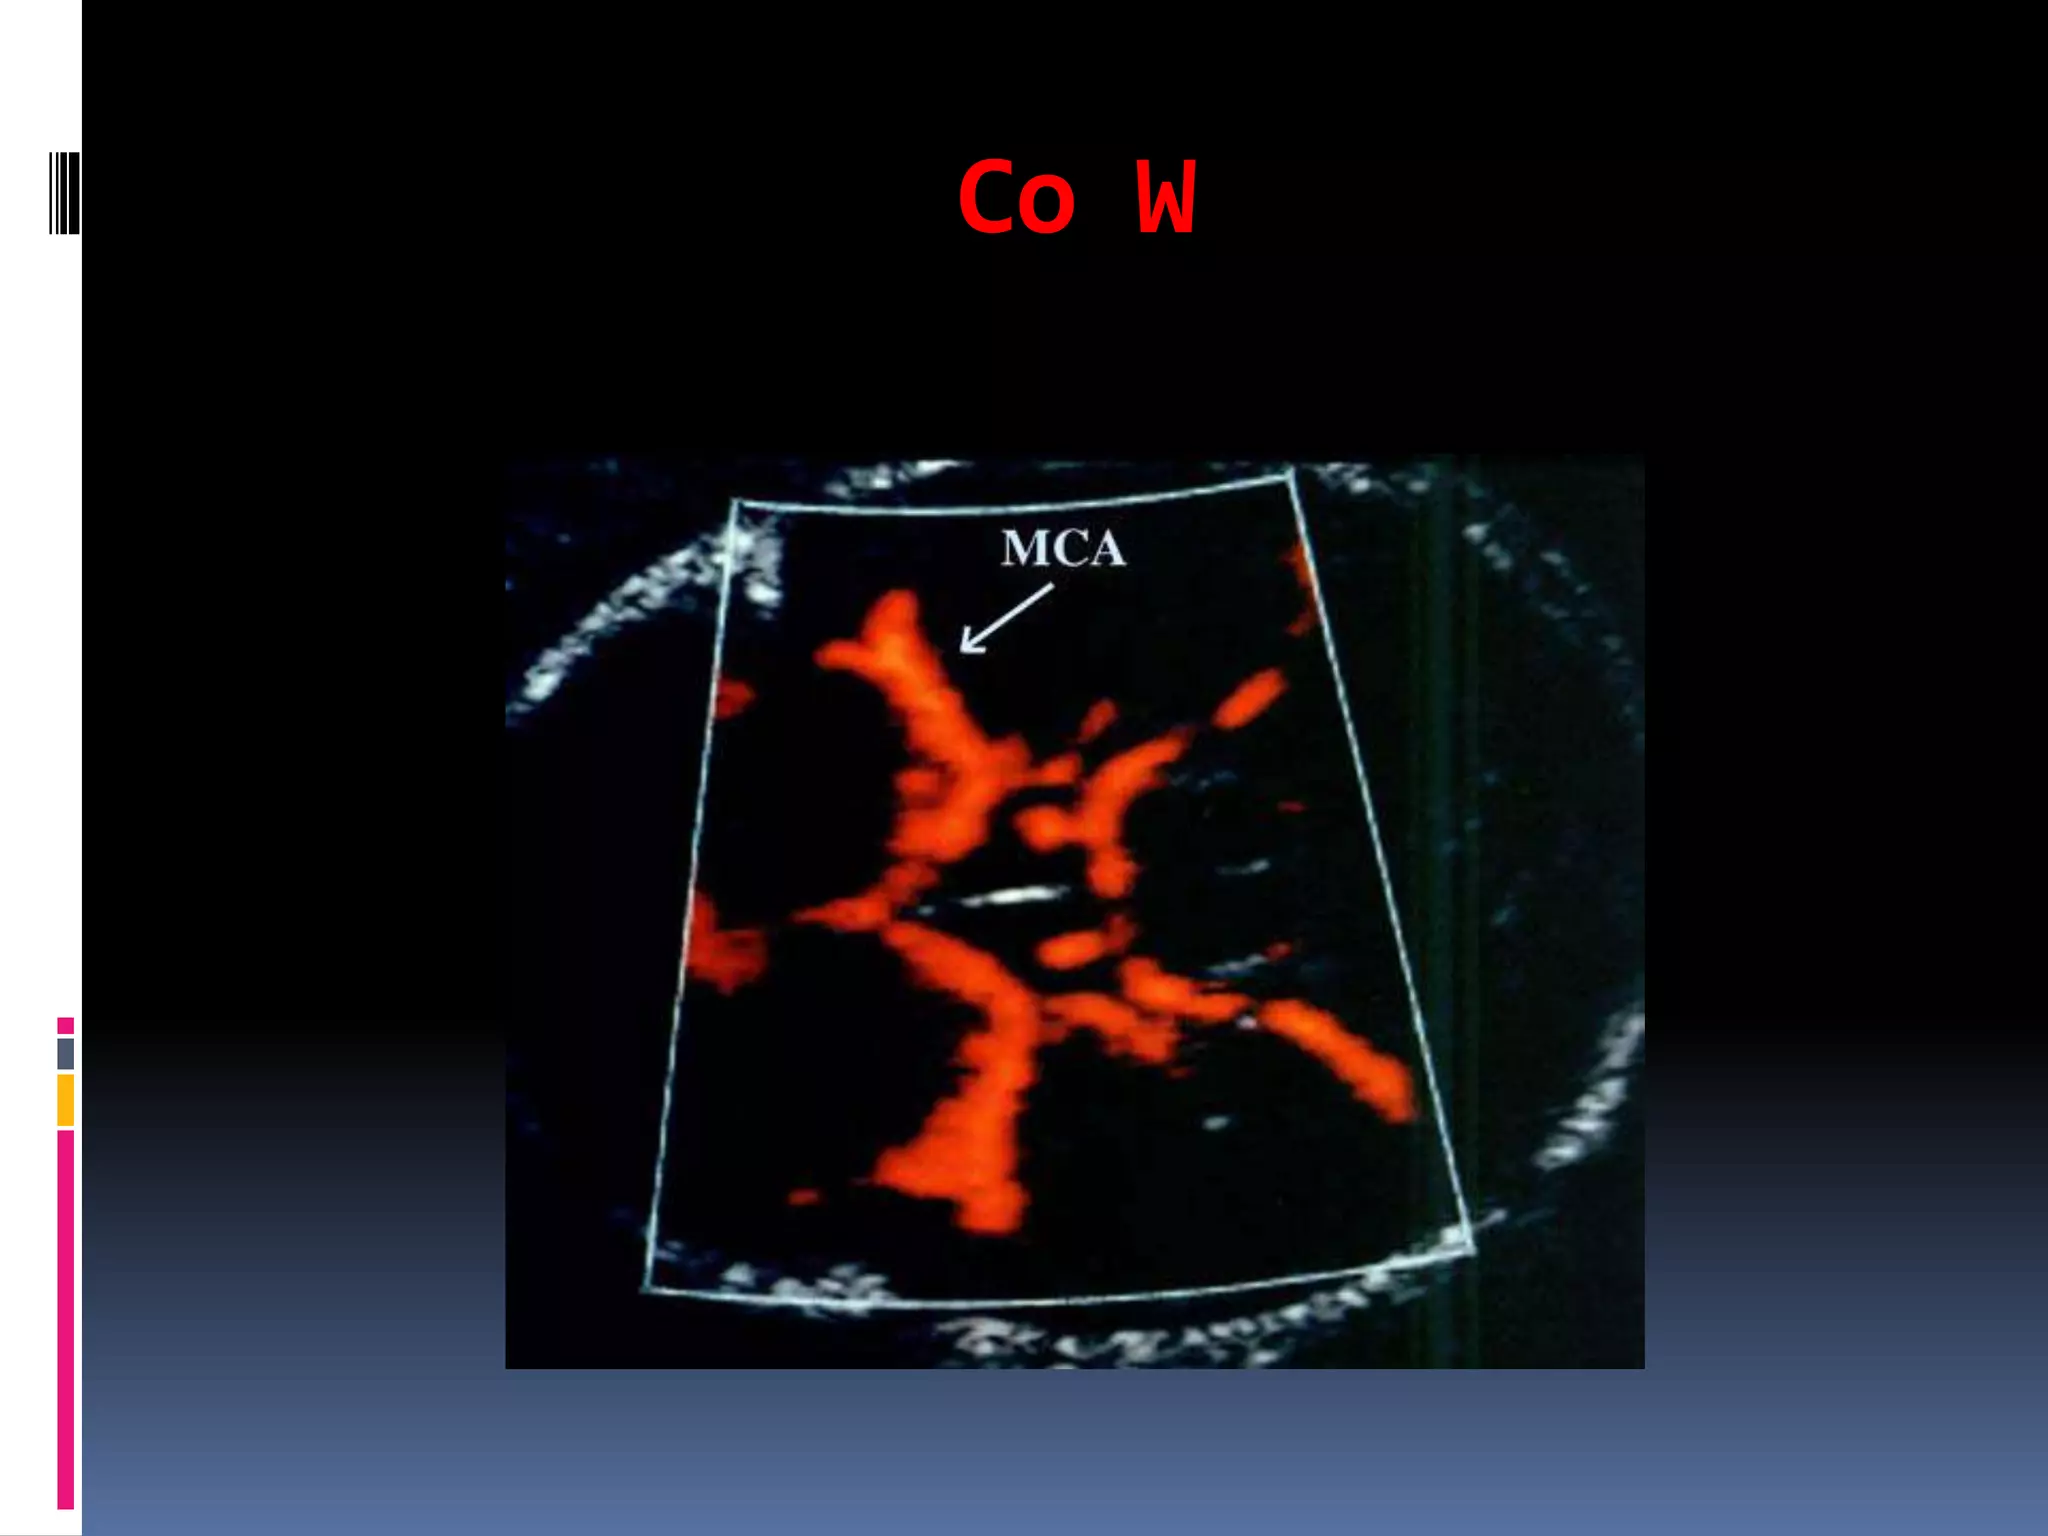

Co W

MCA

Middle cerebral artery Doppler waveforms,

obtained from the proximal portion of the

vessel, immediately after its origin from the

circle ofWillis, have shown the best

reproducibility.